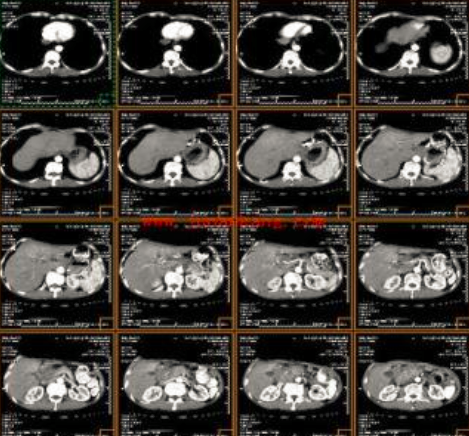

ct打印胶片怎么用远程就医、转院就医时,CT核磁DICOM电子胶片的重要性!【就医知识】_https://www.jmylbn.com_新闻资讯_第2张

(JPEG格式)